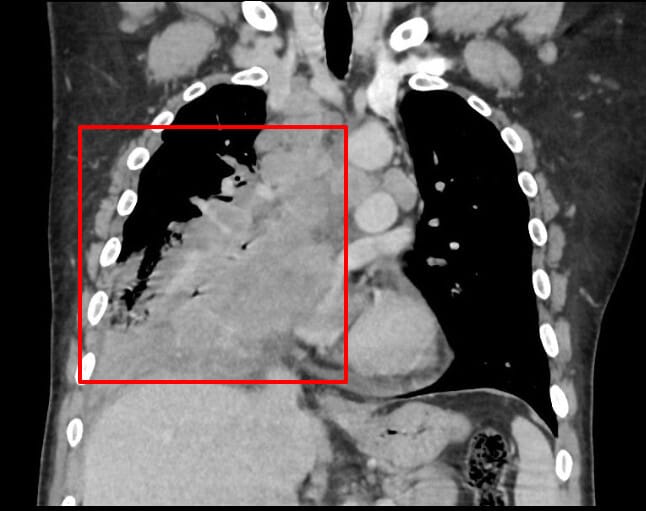

흉부 CT 소견

주로 폐 중심부에 발견, 종격동 림프절 비대 동반

소세포폐암 진단 및 병기 결정에 가장 중요한 영상 검사입니다.

| 중심부 종괴(central mass) |

| 폐문(hilum) 또는 기관지 근처에 조영 증강되는 덩어리성 병변 |

| 종격동 림프절 비대 |

| 대칭적으로 비대해진 림프절이 흔하며, 빠르게 전이됨 |

| 기관지 협착 또는 폐쇄 |

| 종양이 기관지를 압박하거나 막아 폐허탈(무기폐) 유발 |

Glick Y, Small cell lung cancer. Case study, Radiopaedia.org (Accessed on 20 Apr 2025) https://doi.org/10.53347/rID-161374

영상 소견상 특징

- Right lung hilum 쪽에 Large mass with necrotic foci

- Complete RML collapse.

- Large RLL consolidation and interstitial thickening in rest of lobe.

- Large right pleural effusion.